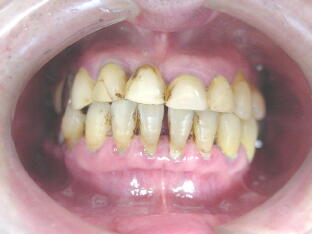

下図の症例写真の歯肉の状態をご覧いただいて、ブラッシングが重要なこ

とは当然ですが、それ以外にもいかに使用する材料によって歯肉に変化が 生じているかについても注目してください。

A、歯周病が進行している上に、低位咬合による前歯部での突き上げ接触が起こり、前歯

がグラグラの状態でした。 ![]() ![]()

奥歯のかみ合わせを挙上して、前歯部での接触をなくし、歯周病の治療に専念した結果、

歯の動揺が収まり、最終補綴物を装着することにより審美状態が改善されました。